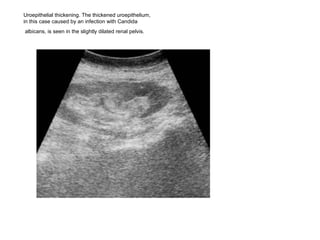

Uroepithelial thickening. The thickened uroepithelium,  in this case caused by an infection with Candida albicans, is seen in the slightly dilated renal pelvis.